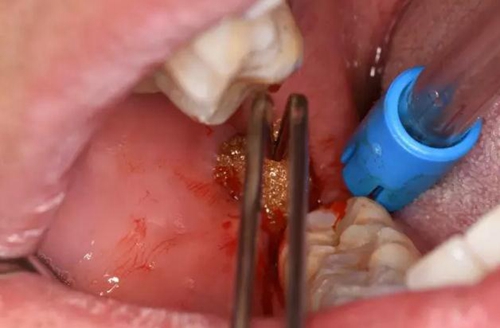

圖10.充分分離膿腔、使膿液盡量排除

(2)口外局部麻醉不要將麻藥注射進(jìn)膿腔內(nèi)

(3)切開部位應(yīng)在膿腫的最低部位,順著皮紋切開

(4)充分分離膿腔,以利于引流通暢,生理鹽水沖洗。